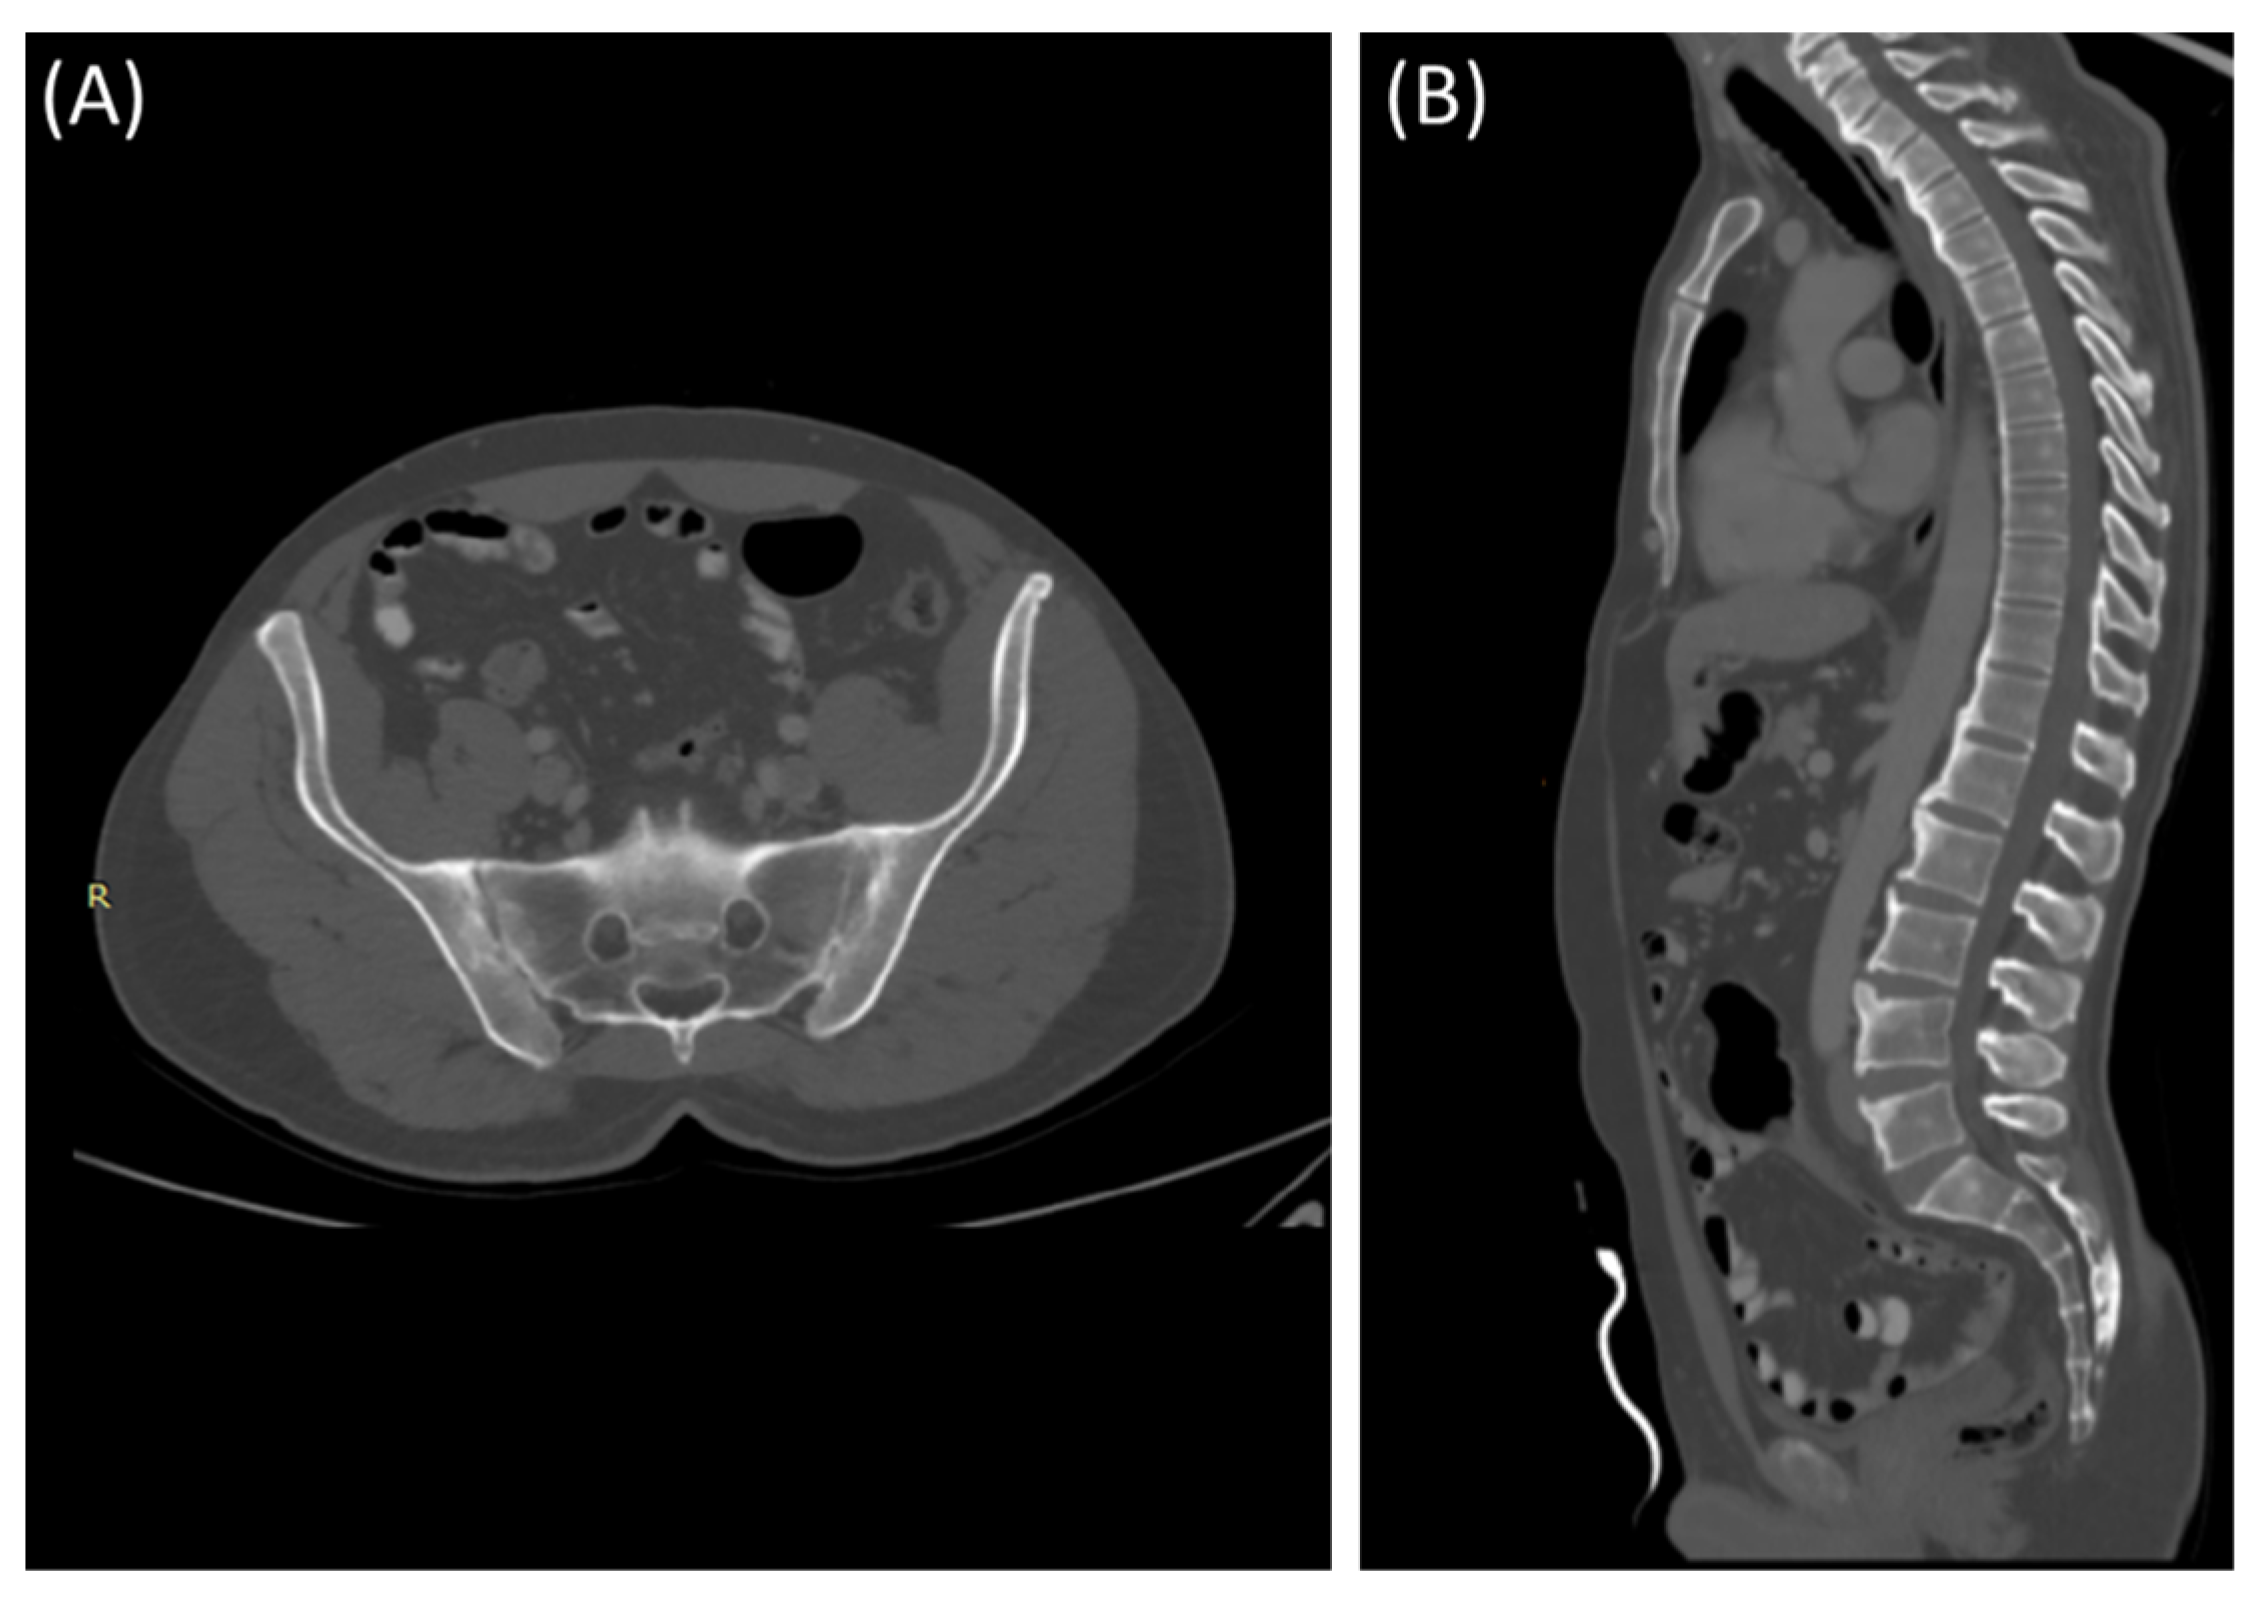

3.3.2. Computed Tomography

CT scans provide more detailed images of the sacroiliac joint and can reveal erosions, sclerosis, and joint space narrowing with greater clarity than X-rays [13]. Severe sacroiliitis, particularly in cases of ankylosing spondylitis, can lead to complete fusion or ankylosis of the sacroiliac joint [4]. CT scans can demonstrate the fusion as a solid, bony bridge between the sacrum and ilium [4]. CT scans can also assess soft tissues surrounding the SIJ, such as ligaments, tendons, and muscles, which may be inflamed in cases of sacroiliitis [44] as demonstrated in Figure 4 and Figure 5.

Figure 5.

Axial bone window CT scan (A) showing Chronic sacroiliitis with ankyloses of the sacroiliac and a sagittal bone window CT scan (B) showing Syndesmophytes in the spine in a 55-year-old patient with Ankylosing spondylitis.

CT scans can provide detailed information about adjacent structures, such as the lumbar spine, hip joints, and pelvic bones, to evaluate for any associated abnormalities or complications [48].